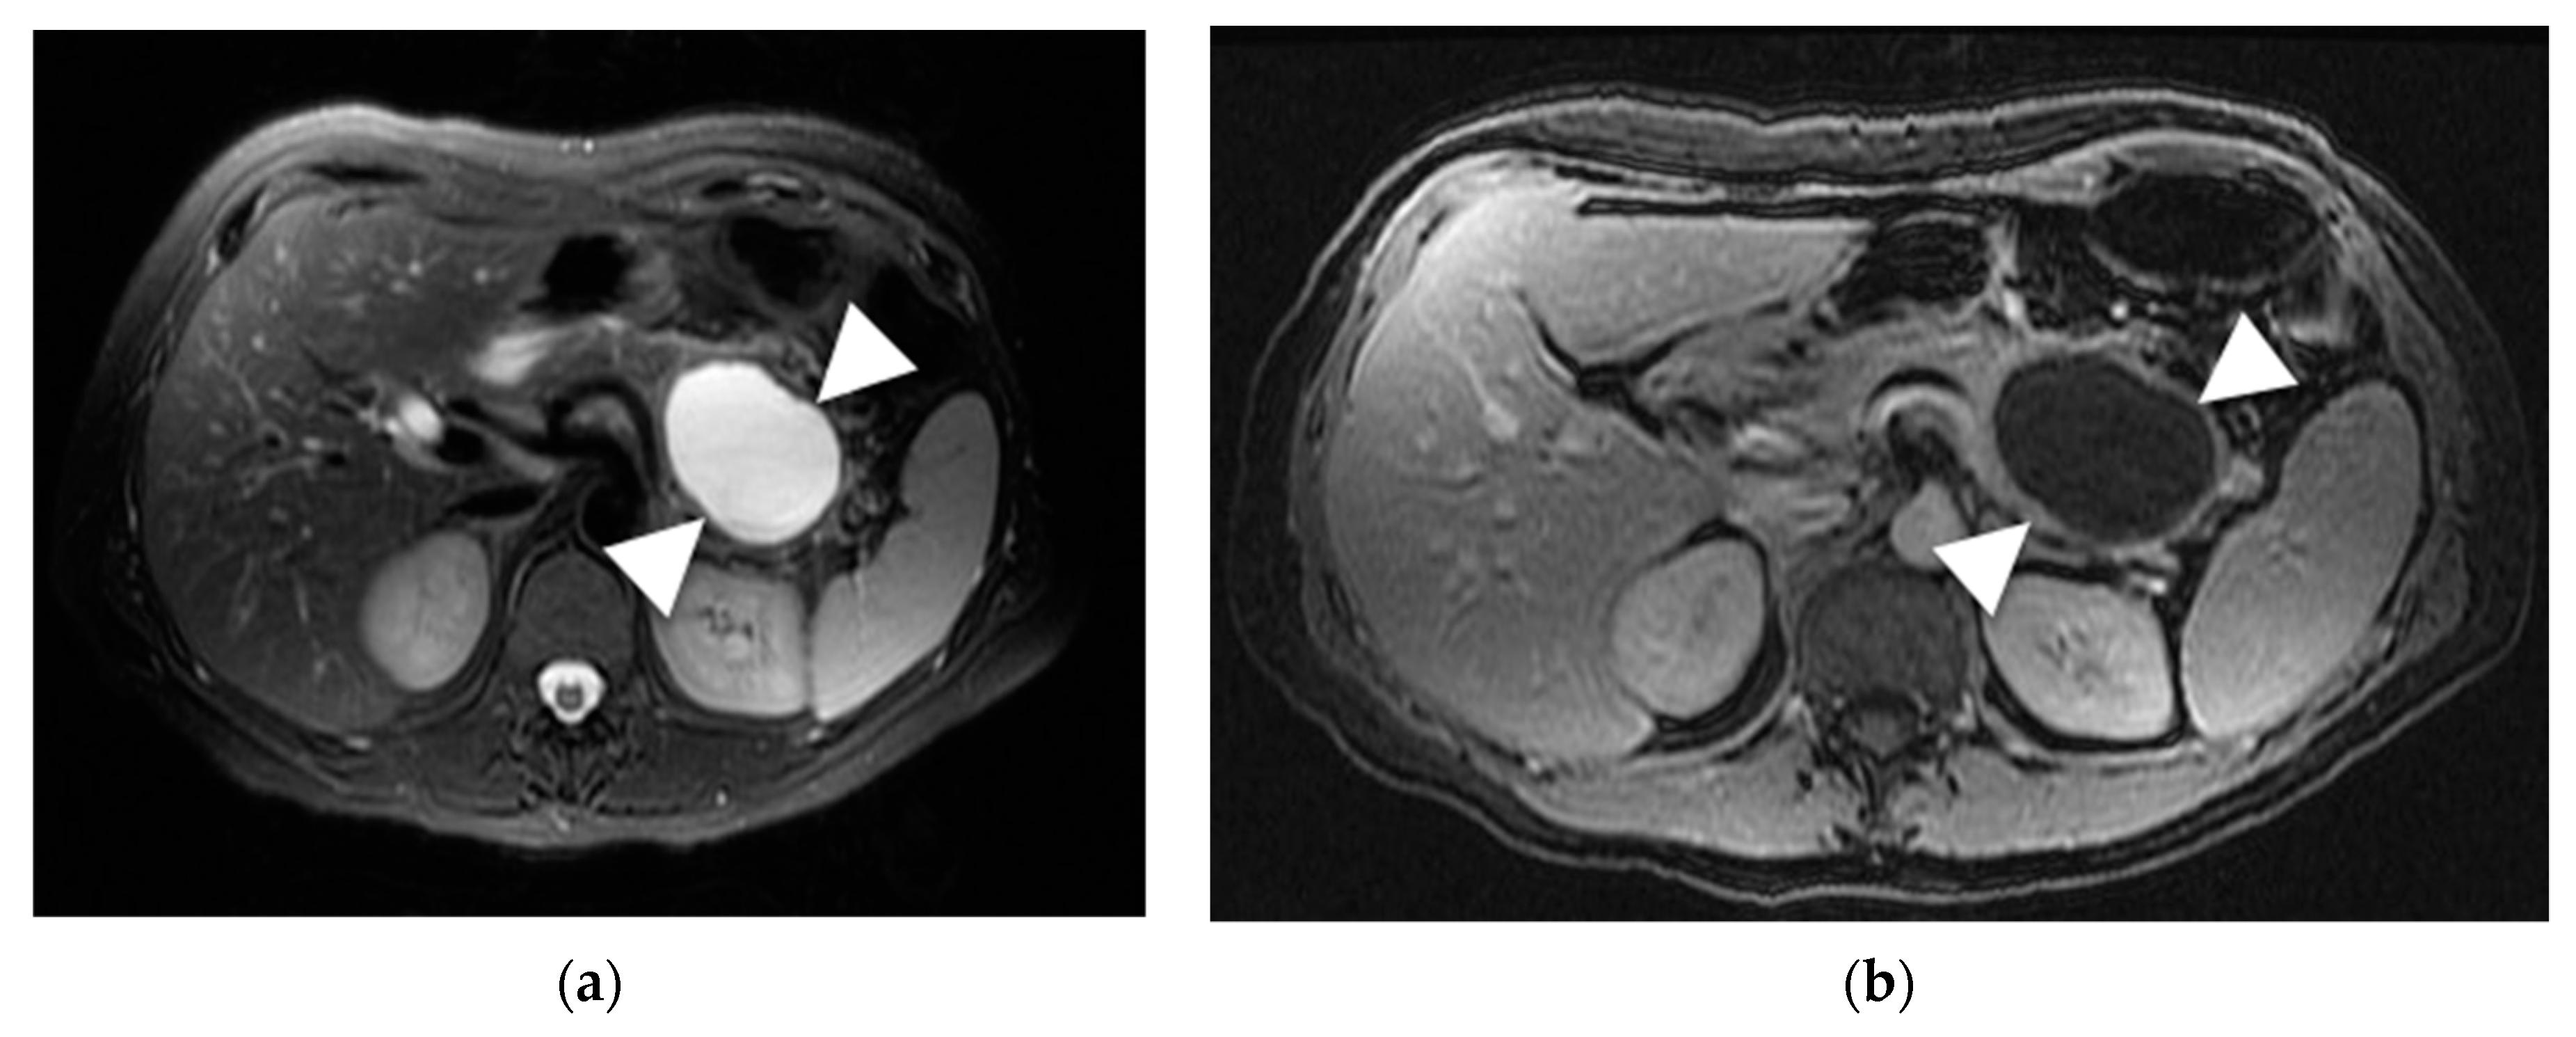

- Choi, J.Y.; Kim, M.J.; Lee, J.Y.; Lim, J.S.; Chung, J.J.; Kim, K.W.; Yoo, H.S. Typical and atypical manifestations of serous cystadenoma of the pancreas: Imaging findings with pathologic correlation. AJR Am. J. Roentgenol. 2009, 193, 136–142. [Google Scholar] [CrossRef] [PubMed]

- Giambelluca, D.; Bruno, A.; Picone, D.; Midiri, M. The honeycomb pattern of pancreatic serous cystadenoma. Abdom. Radiol. 2019, 44, 1191–1192. [Google Scholar] [CrossRef]